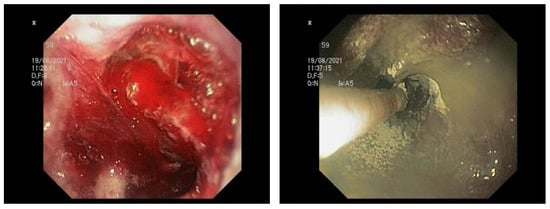

4.2. Is HP a Possible Gold Standard in Malignancy-Related NVUGIB?